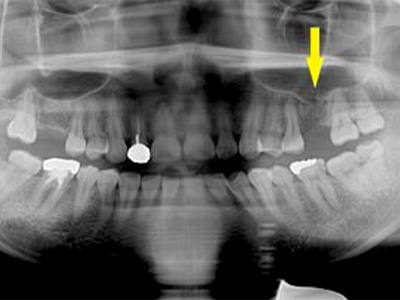

患者様は50代男性。インプラント治療前のレントゲン写真です。

右下顎大臼歯2本の抜歯後のレントゲン写真で、写真の黄色矢印は、歯の周囲の歯槽骨が大きく吸収されてしまっていました(黄色矢印)。 -

CTで見ると、骨吸収の様子が良く分かり、下顎骨の中を通る神経近くまで骨がありませんでした(黄色矢印)。